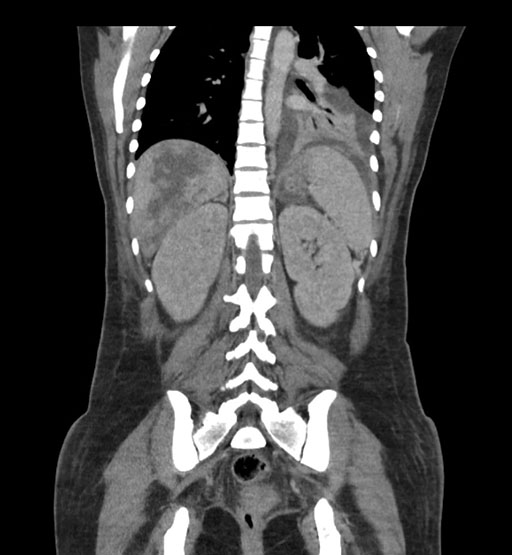

Coronal Arterial

Imaging analysis

Based on initial findings, which issue(s) would you be most concerned about?